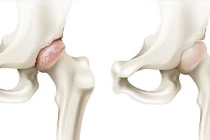

SuperPath là một trong kỹ thuật thay khớp háng tiên tiến nhất hiện nay. Phương pháp này được chỉ định phẫu thuật rộng rãi các bệnh lý khớp háng khác nhau như: hoại tử chỏm xương đùi, thoái hóa khớp háng, gãy cổ xương đùi...